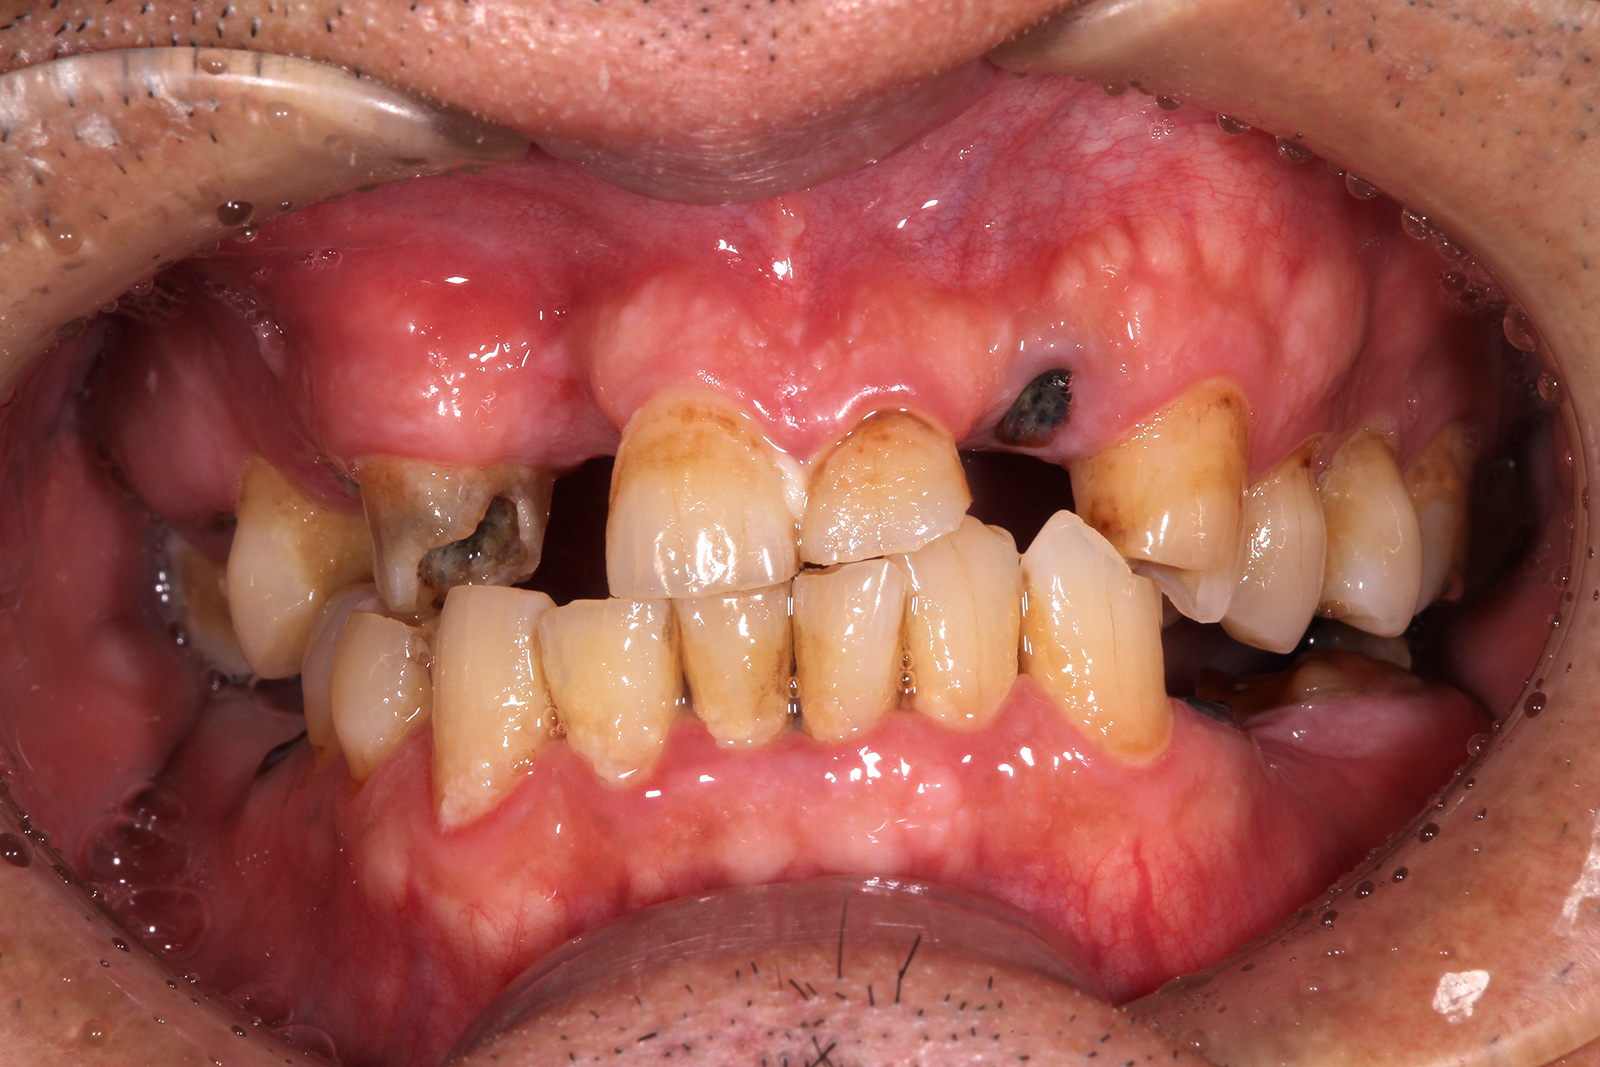

• 治療前

• 治療後

お口全体の治療。インプラント治療の他、ブロック骨移植や結合組織移植、全顎矯正などを行った。治療期間は2年6ヶ月ほど。費用はおよそ500万円。定期的なメンテナンスを行わないと、インプラント周囲炎のリスクがある。